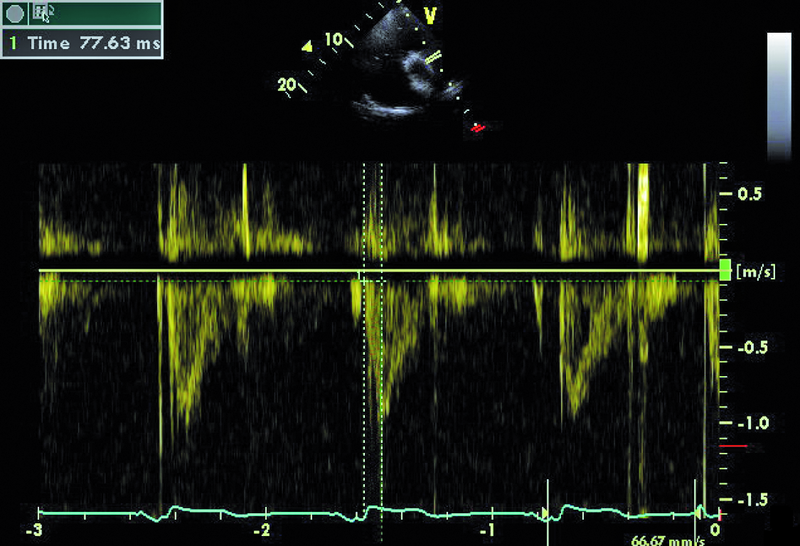

Mężczyzna, lat 59. Jakie patologie można rozpoznać na rycinach?

5. Nadciśnienie płucne (ryc. 4).